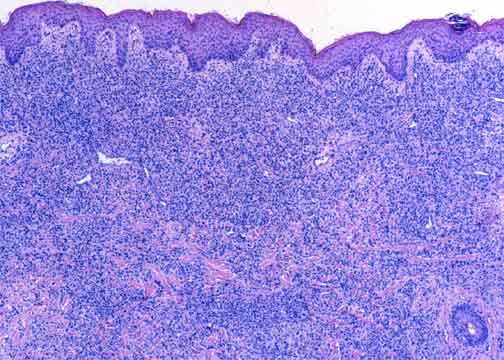

This is a subsequent biopsy from the same patient as Example 2A. Note how the lymphoma has progressed to a more aggressive morphology, both architecturally and cytologically.

The atypical T-cell infiltrate involves the entire dermis and (though not

seen here) the superficial subcutis. The epidermis is spared, with a

pale, uninvolved Grenz zone in the immediately subjacent dermis. |

A mixture of small and large atypical cells is present. Notice how

the lymphoma has progressed from the earlier specimen

(Example 2A). The infiltrate is

much denser and the cells larger and more atypical. The nuclei of the larger

cells are twisted or convoluted rather than oval or cleaved as

would be seen in most B-cell lymphomas. |